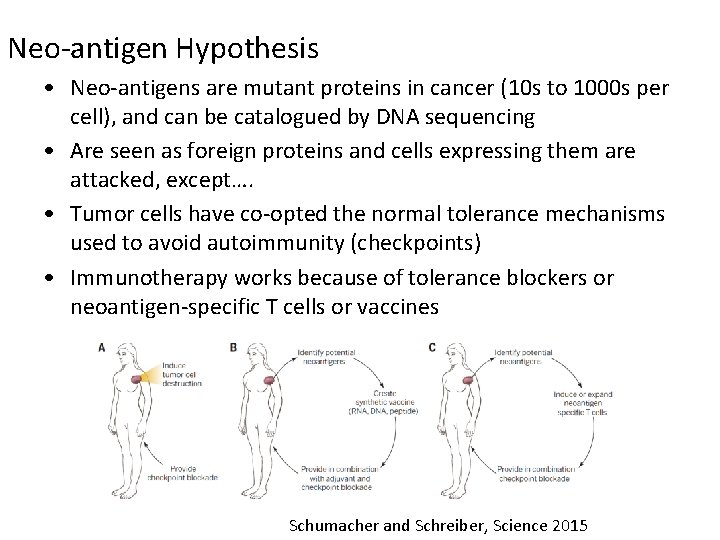

Neo-antigen Hypothesis • Neo-antigens are mutant proteins in cancer (10 s to 1000 s per cell), and can be catalogued by DNA sequencing • Are seen as foreign proteins and cells expressing them are attacked, except…. • Tumor cells have co-opted the normal tolerance mechanisms used to avoid autoimmunity (checkpoints) • Immunotherapy works because of tolerance blockers or neoantigen-specific T cells or vaccines Schumacher and Schreiber, Science 2015